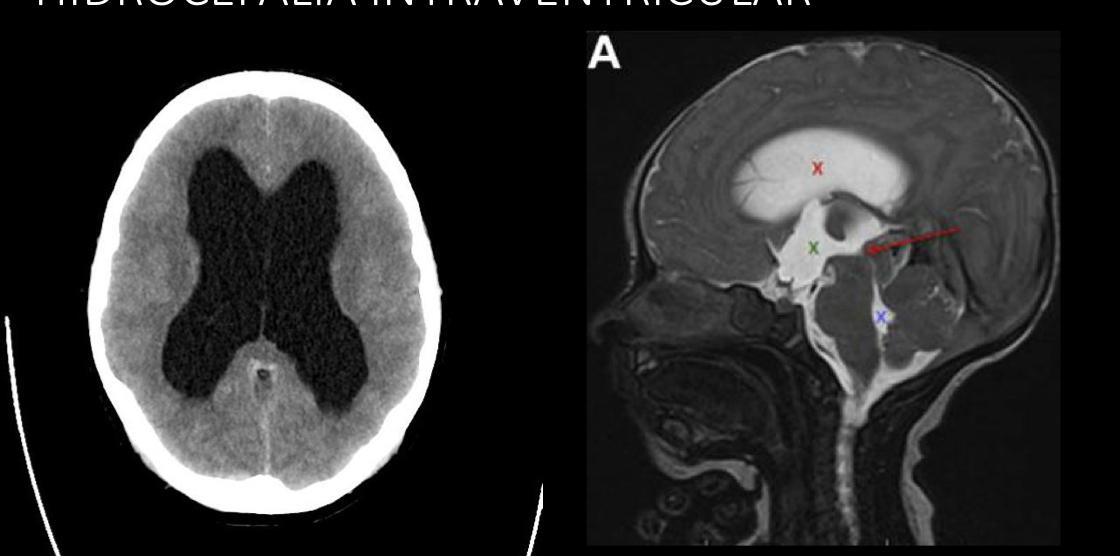

imagen para no comunicante

A

RM

TC

q se ve en RM no comunicante

dilatación proximal a la obstrucción

NO comunicante

Intraventricular

Estenosis acueducto de Silvio